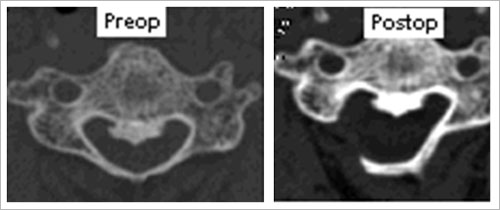

¢Á ÀåÁ¡ : ô¼öÁõ(ôÃß°üÀÌ Á¼¾ÆÁ® ½Å°æ¿¡ ´ëÇÑ ½ÉÇÑ ¾Ð¹ÚÀ¸·Î

ÁßÃ߽Űæ°è Áõ»óÀÌ ¹ß»ý µÈ

°Í) ȯÀÚÀÇ °æ¿ì¿¡ ½Ã¼úµÇ´Â ¼ö¼úÀ̸ç ÈÄ¹æ µµ´Þ¹ýÀ» ÅëÇÏ¿© Á¼¾ÆÁø ôÃß°ü À»

³ÐÇô ÁÜÀ¸·Î½á ½Å°æÀÇ ¾Ð¹ÚÀ» Ç®¾îÁÖ°í ¿îµ¿ ºÐÀýÀ» À¯ÇÕÇÏÁö ¾Ê¾Æ ¿îµ¿¼º º¸Á¸°ú

°æÃßÀÇ ¾ÈÀü¼ºÀ» È®º¸ÇÒ ¼ö ÀÖ½À´Ï´Ù.